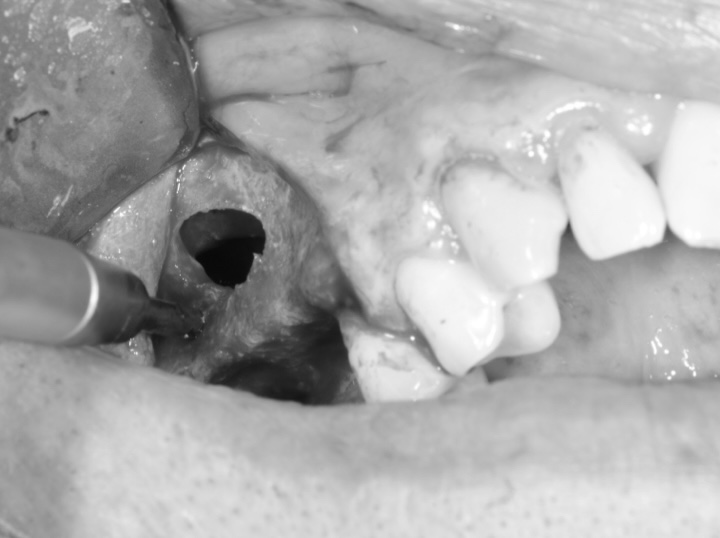

Lors d’une technique couramment utilisée, une incision est réalisée au niveau de la gencive, dans la région des prémolaires ou molaires supérieures, afin d’accéder à l’os maxillaire. Une fenêtre osseuse est ensuite créée pour permettre le soulèvement délicat de la membrane sinusienne. Un matériau de greffe osseuse est alors placé sous cette membrane afin de soutenir la formation osseuse. Le matériau de greffe peut être constitué d’os autogène, d’os d’origine donneur ou de substituts synthétiques conçus pour favoriser la régénération osseuse.